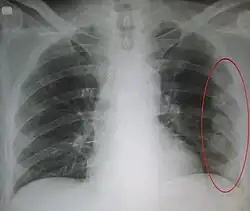

Right sided pneumothorax and rib fractures -